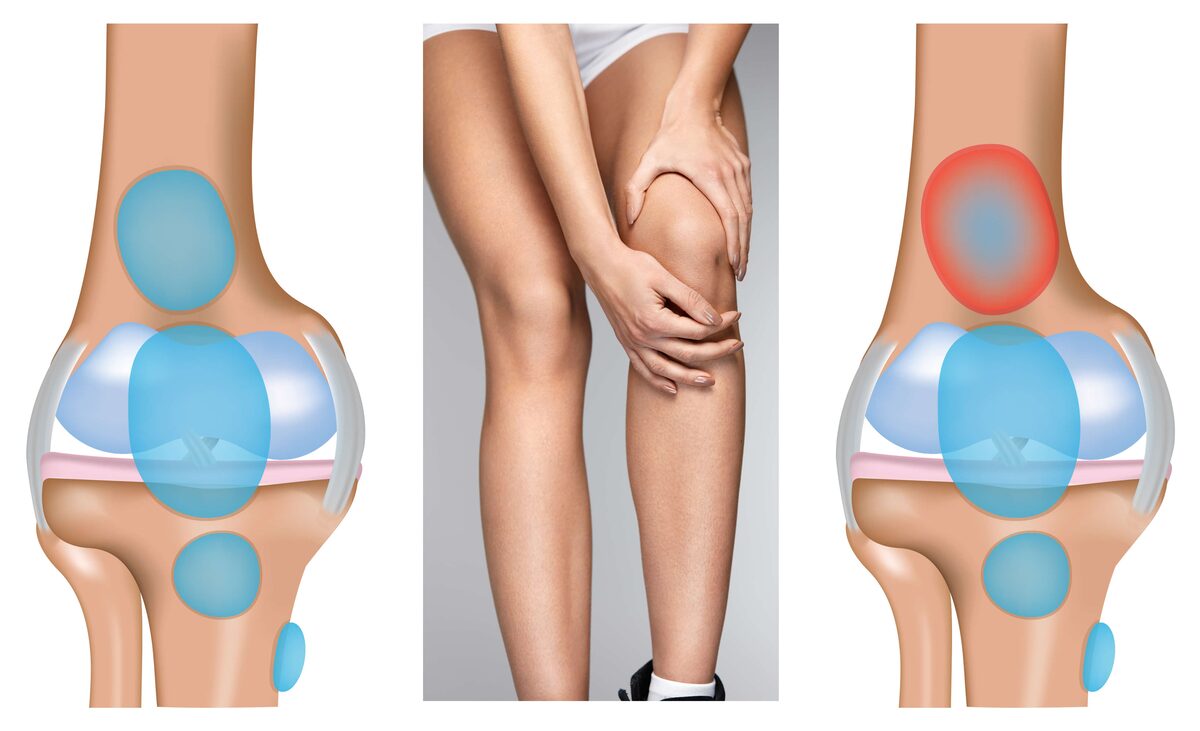

Заболевание сустава: симптомы и лечение